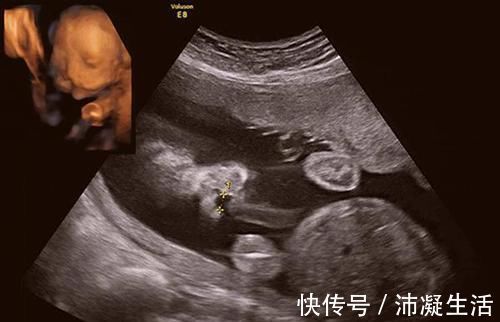

王女士|35岁宝妈怀上“畸形儿”,不顾医生劝告坚持要生,网友:自找苦吃

【 王女士|35岁宝妈怀上“畸形儿”,不顾医生劝告坚持要生,网友:自找苦吃】今年35岁的王女士,经过十分漫长的备孕,终于怀上了孩子。家人都感到特别的高兴,因为她在这个年龄间怀上孩子实属不易。

但前天王女士到医院做产检的时候,医生却告诉她:“这胎是个畸形胎,不建议王女士把孩子留下来。”王女士听到这个消息后顿时愣住了:自己努力了这么久,好不容易怀上怎么会是个畸形胎呢?

原来王女士是因为吃了杏仁,所以导致孩子畸形,最后王女士因为年龄方面的原因,还是决定把这个孩子生下来,但是生下孩子后,家里人需要承担的压力也可想而知。